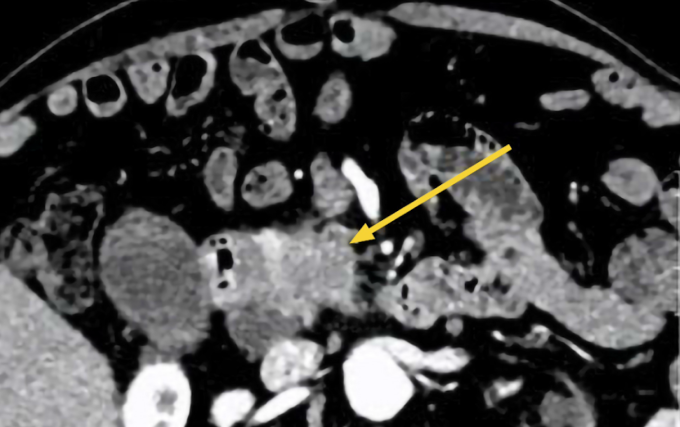

Kết quả siêu âm ổ bụng cho thấy vùng đầu tụy có cấu trúc giảm âm kích thước khoảng 70 mm, kèm phù nề mô xung quanh. Thân, đuôi tụy có một số tổn thương nhỏ hơn. Hình ảnh CT bụng ghi nhận tổn thương tại vùng đầu tụy gây giãn đường mật trong và ngoài gan, bác sĩ nghi ngờ ác tính. Khối u có ranh giới không rõ với đoạn D2 của tá tràng (đoạn đầu của ruột non). Túi mật căng, trong lòng có sỏi, bùn mật, một số hạch quanh đầu tụy, rốn gan.

Chụp CT cho thấy đầy tụy tổn thương (mũi tên vàng) của ông Hưng. Ảnh: Bệnh viện Đa khoa Tâm Anh